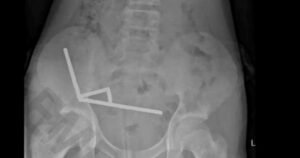

Un adolescente se tragó casi 200 imanes que compró por internet y perdió parte de su intestino

Los imanes más peligrosos del mercado se le unieron dentro del cuerpo.¿Qué son los imanes de neodimio...